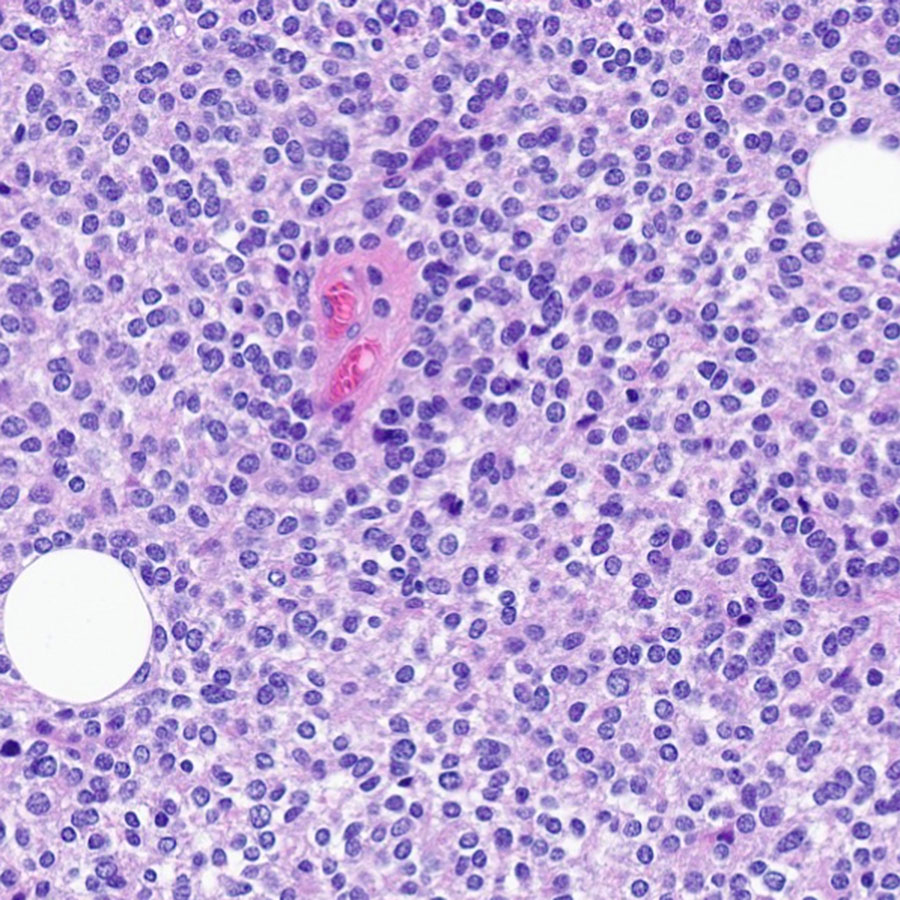

You don’t need special stains or fancy molecular testing to diagnose this #brain #tumor, located in the fourth ventricle. Flex your histology skills and tell me what you see! @NU_Pathology #neuropath πŸ§ πŸ”¬

7

27

110